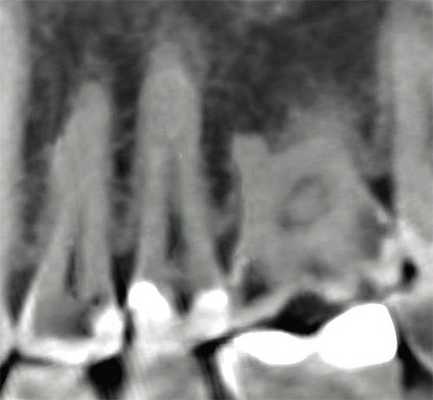

2. Патологии в периапикальных тканях

Наиболее частым патологическим состоянием, затрагивающим зубы является воспалительные процессы пульпы и периапикальных областей. Технология КЛКТ теперь предоставляет клиницисту возможность обозревать нужную зону в трех различных плоскостях, тем самым получая 3D информацию. Поражения, заключенные в губчатом веществе кости с малым количеством или отсутствием кортикальной пластинки, на обычной пленке могут быть диагностированы с большим трудом. Lofthag-Hansen, Stavropoulos и Wenzel сравнили точность получаемых данных при КЛКТ с ограниченным FOV и обычными снимками.

Ученые сообщили, что КЛКТ предоставляет более точные диагностические данные (61%) по сравнения с цифровыми (39%) и обычными (44%) рентгенограммами. Но, несмотря на то, что данные КЛКТ являются более точными, исследователи не призывают к полному вытеснению обычной внутриротовой рентгенографии для выявления периапикальных изменений в обычной клинической практике из-за финансовой и вредностной составляющих. Estrela и коллеги предложили использовать периапикальные индексы, основанные на КЛКТ, для идентификации патологий (Фото 4-6).

Фото 5: Хронические периапикальные абсцессы около первого правого нижнего моляра

Фото 6: Поражение периодонтальных тканей около левого верхнего второго моляра

Система индексов КЛКТ состоит из 6 ступеней (0-5), исходящих из определения самого большого размера повреждения в каком либо из измерений, и принятие в расчет расширение и разрушение кортикальной кости.